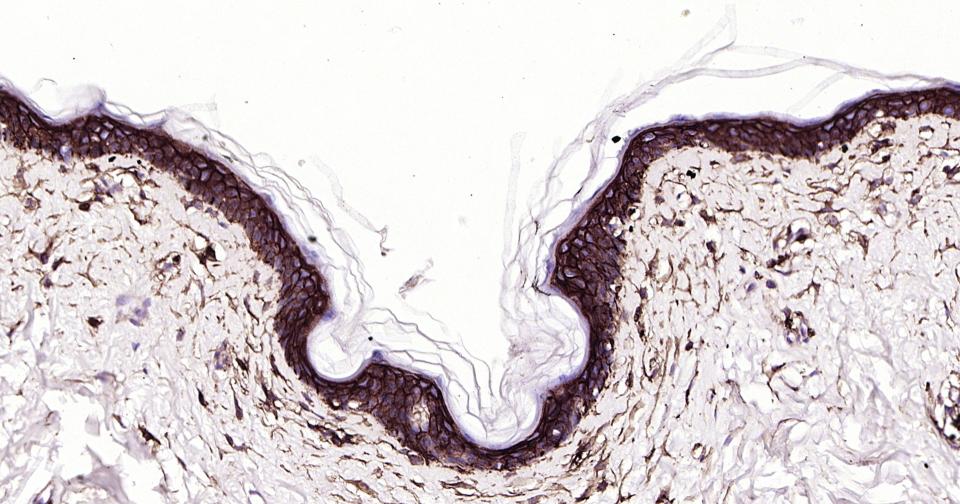

| IHC-P | Human | 1:100-500 | |